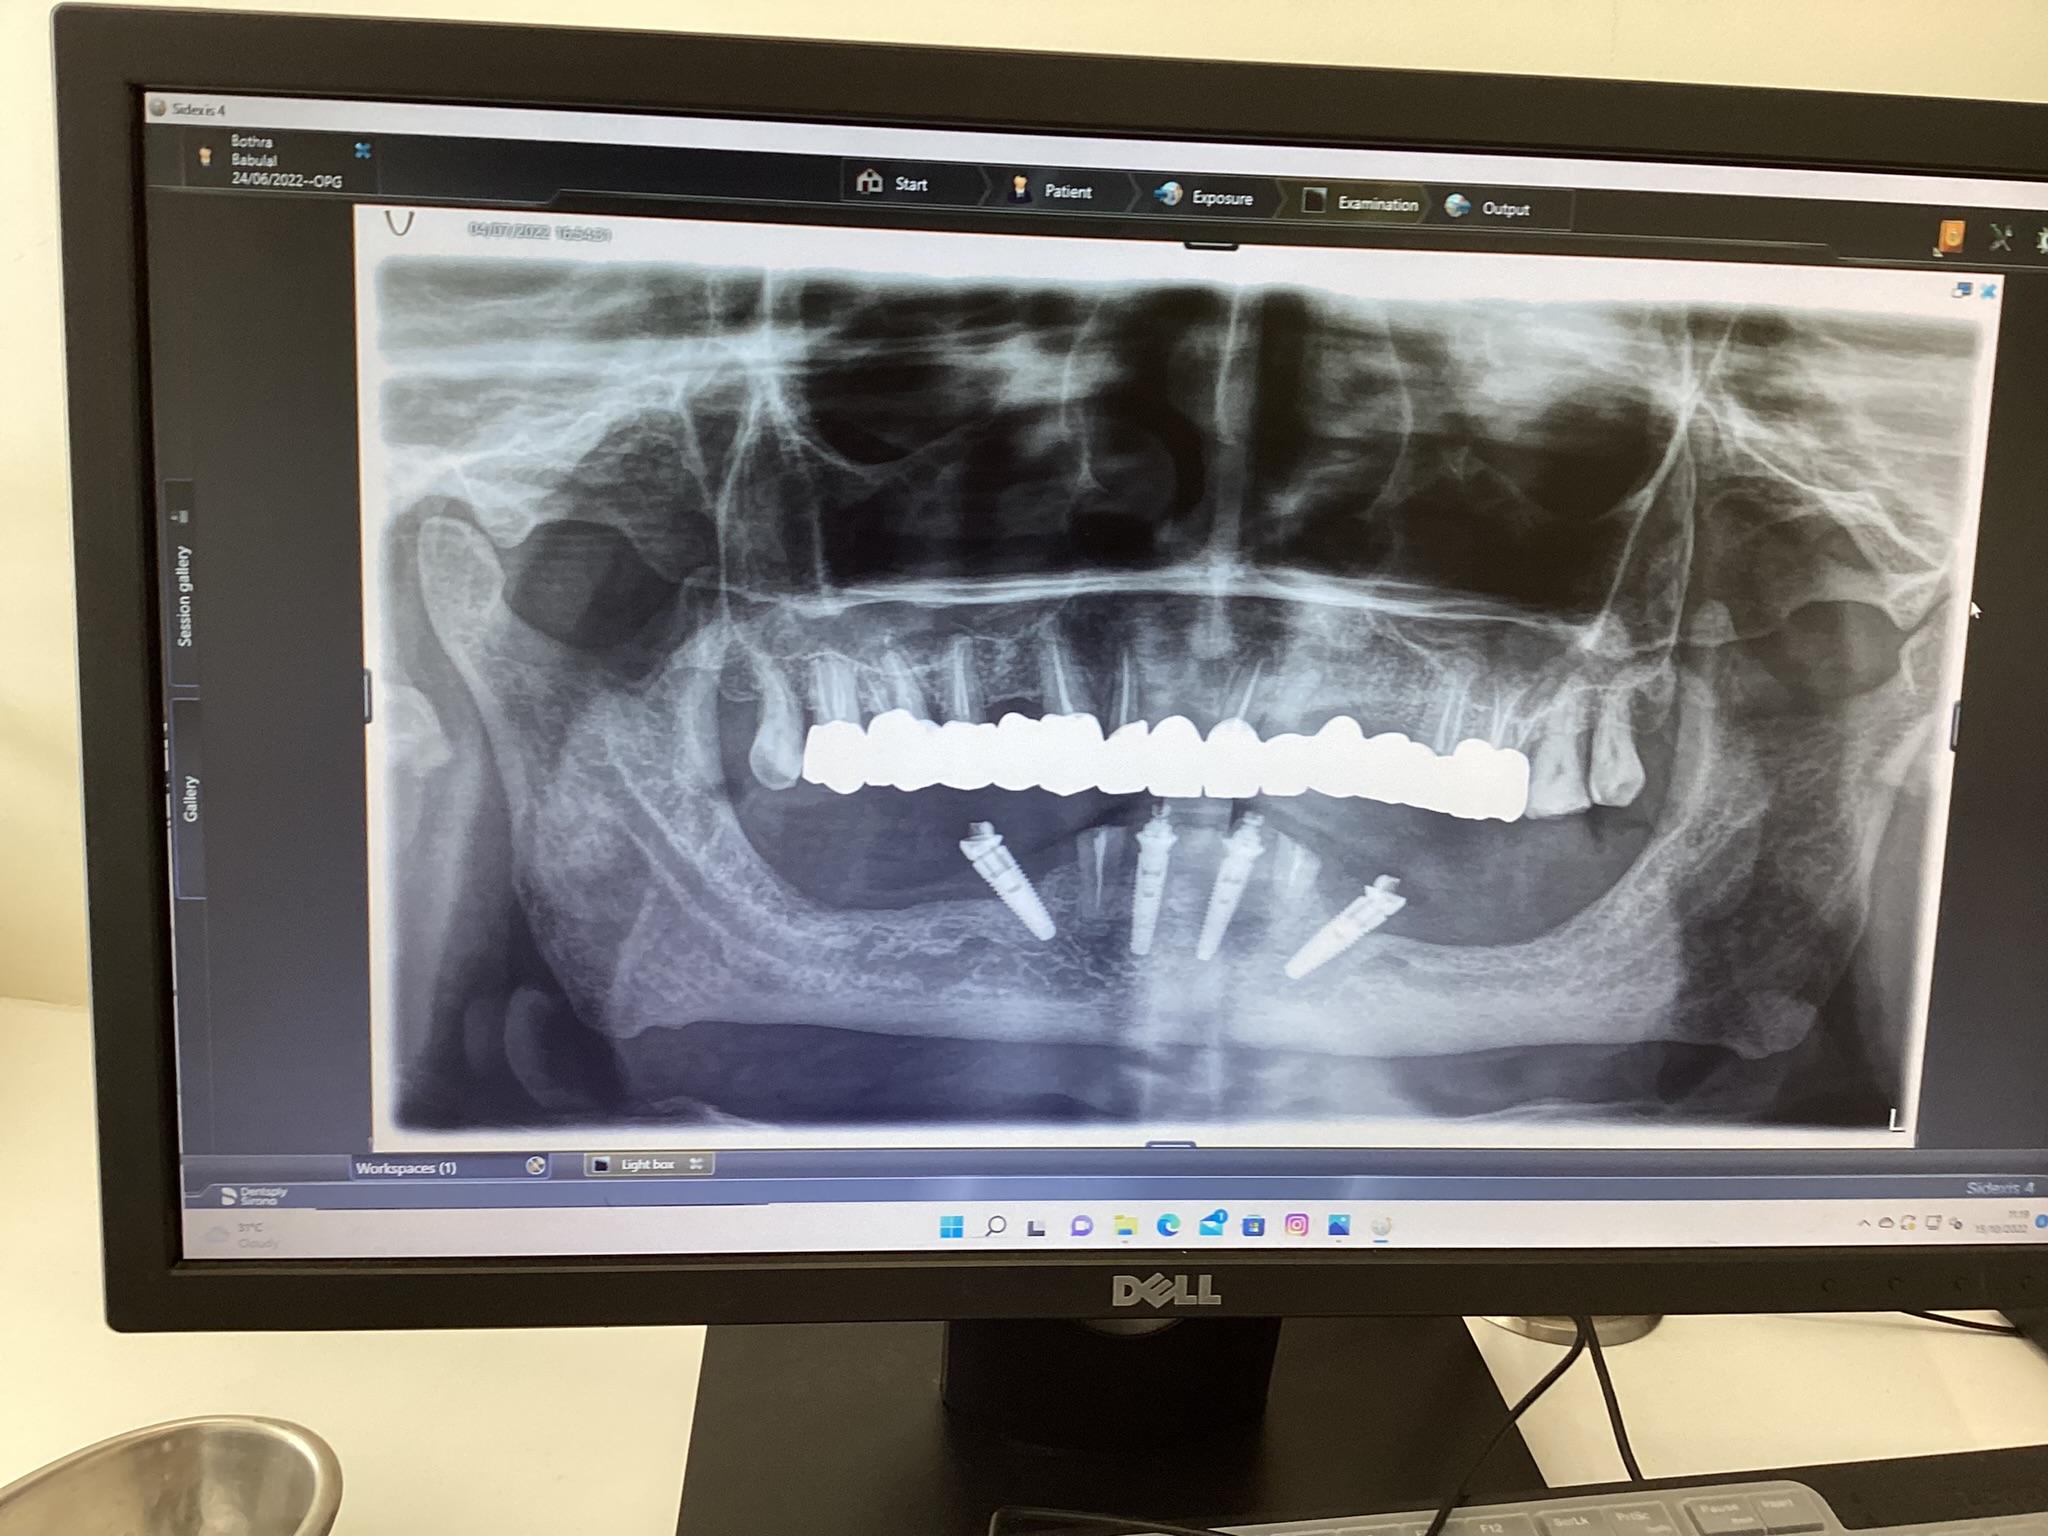

3. X-rays

In some cases, X-rays may be needed to get a clearer view of your teeth, roots, and jawbone. These images help in identifying hidden problems like impacted teeth, bone loss, or infections that might not be visible during the initial examination.

In addition to routine dental check-ups, Dentasia offers specialized dental examinations for specific needs: Orthodontic Check-ups: For patients requiring braces or aligners, our orthodontic dental check-ups are designed to assess the alignment of teeth and jaw, offering treatment plans to correct misalignment. Dental Implants: For those considering dental implants, we offer specialized check-ups that evaluate your jawbone health and determine the best course of action for implant placement. Senior Citizens: We provide dental checks tailored to senior citizens, focusing on age-related issues such as gum recession, tooth wear, and dental prosthetics. Click here to know more about dental implants and bridges.